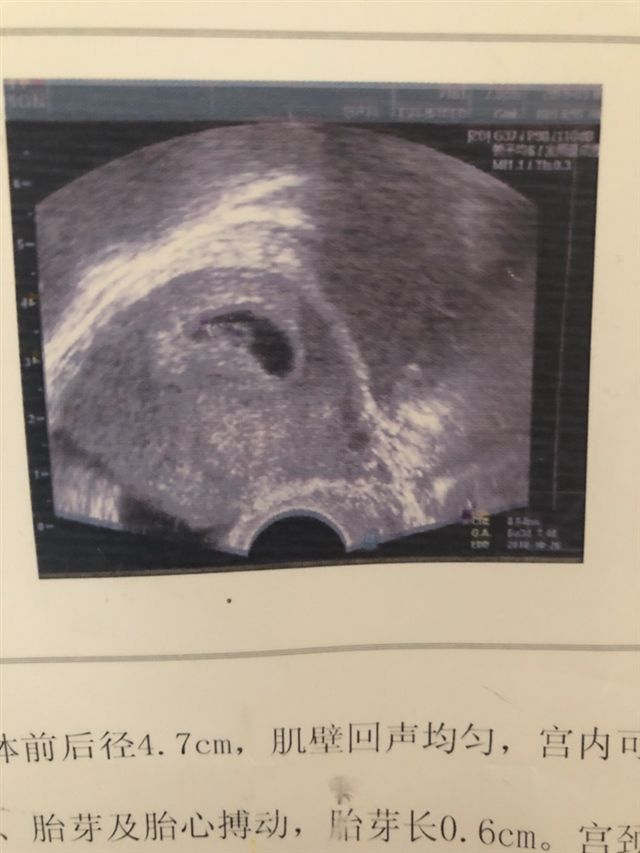

唐小宝[帖主]:这是怀孕6周的时候检查的B超